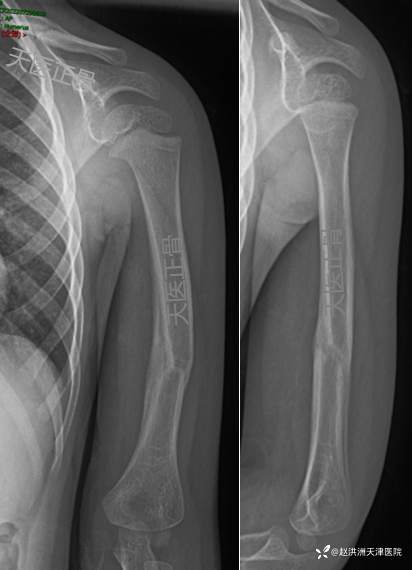

8周影像:锁骨、肱骨骨痂开始塑型

12周力线矫正良好

伤后6个月,骨折痕迹几乎消失